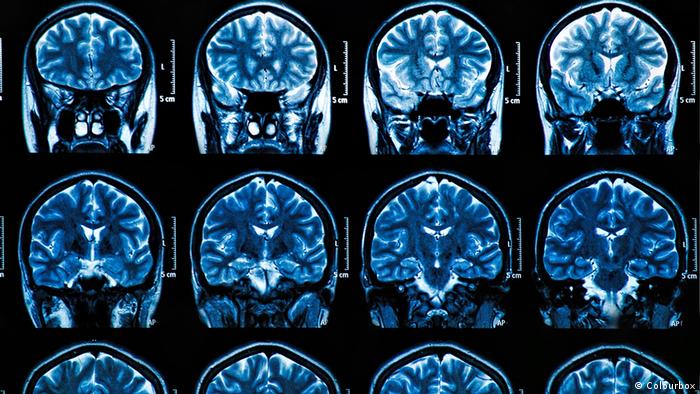

En la enfermedad de alzheimer, dos proteínas clave -la tau y la beta-amiloide- se acumulan gradualmente de forma anormal en el cerebro, provocando la muerte de las células cerebrales y el encogimiento del cerebro, lo que provoca la pérdida de memoria y una creciente incapacidad para realizar las tareas cotidianas.